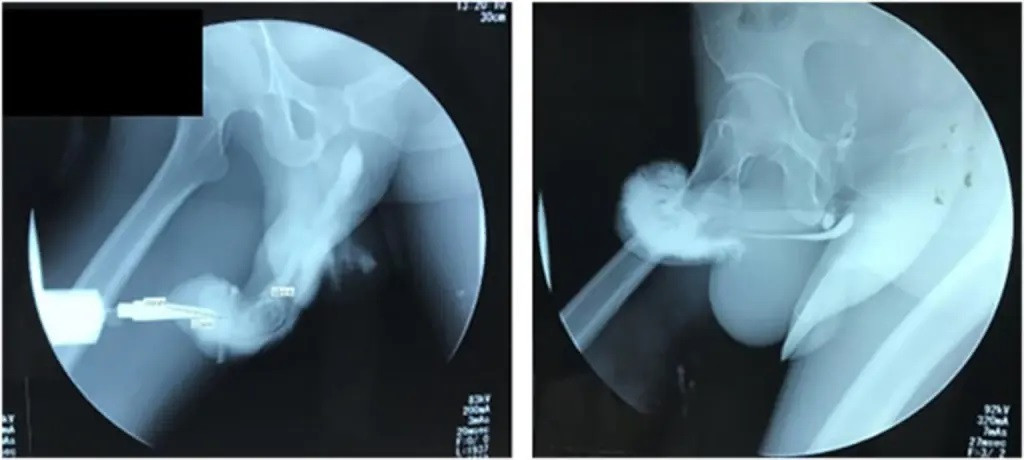

![]() |

| Ảnh chụp X-quang cho thấy dương vật bị gãy của một người đàn ông Indonesia khác từ tháng 7 năm 2022. Nguồn:Tạp chí Phẫu thuật Quốc tế |

Một cuộc kiểm tra sau đó xác nhận bệnh nhân thực sự bị "gãy dương vật rộng và sâu" trong khi mô dương vật cũng bị đứt. Một vết thương ở thành mạch máu khiến máu rỉ ra các mô xung quanh. Đó là lý do tại sao người đàn ông này đi tiểu ra máu trước đó.

Các tác giả nghiên cứu cho biết, những vết nứt dương vật như vậy xảy ra khi dương vật cương cứng bị cong vênh sau khi va chạm mạnh vào đáy chậu hoặc xương mu trong quá trình hoạt động tình dục mạnh mẽ.